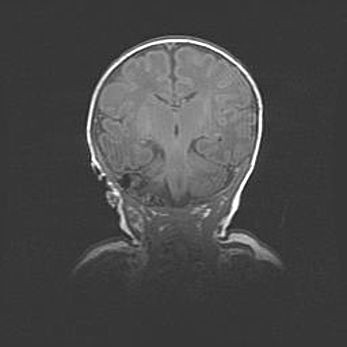

Сообщающаяся гидроцефалия. Кистозная энцефаломаляция головного мозга.

Возраст: 3 месяца 4 дня

Вес: 3100 г

Пол: женский

Окружность головы: 34 см

Срок гестации: 31 неделя

Кистозная энцефаломаляция головного мозга - одна из форм поражения головного мозга в детском возрасте. Характеризуется возникновением множественных и распространённых кист в коре, белом веществе и подкорковых образованиях головного мозга у плодов, новорождённых и детей раннего возраста. Развитие кистозной энцефаломаляции связано с внутриутробной асфиксией и гипотонией, родовой травмой, тромбозом синусов, пороками развития сосудов, инфекциями, сепсисом и другими причинами. Наиболее значимые инфекционные агенты: вирусы простого герпеса, цитомегалии, краснухи, токсоплазмы, энтеробактерии, золотистый стафилококк и другие.